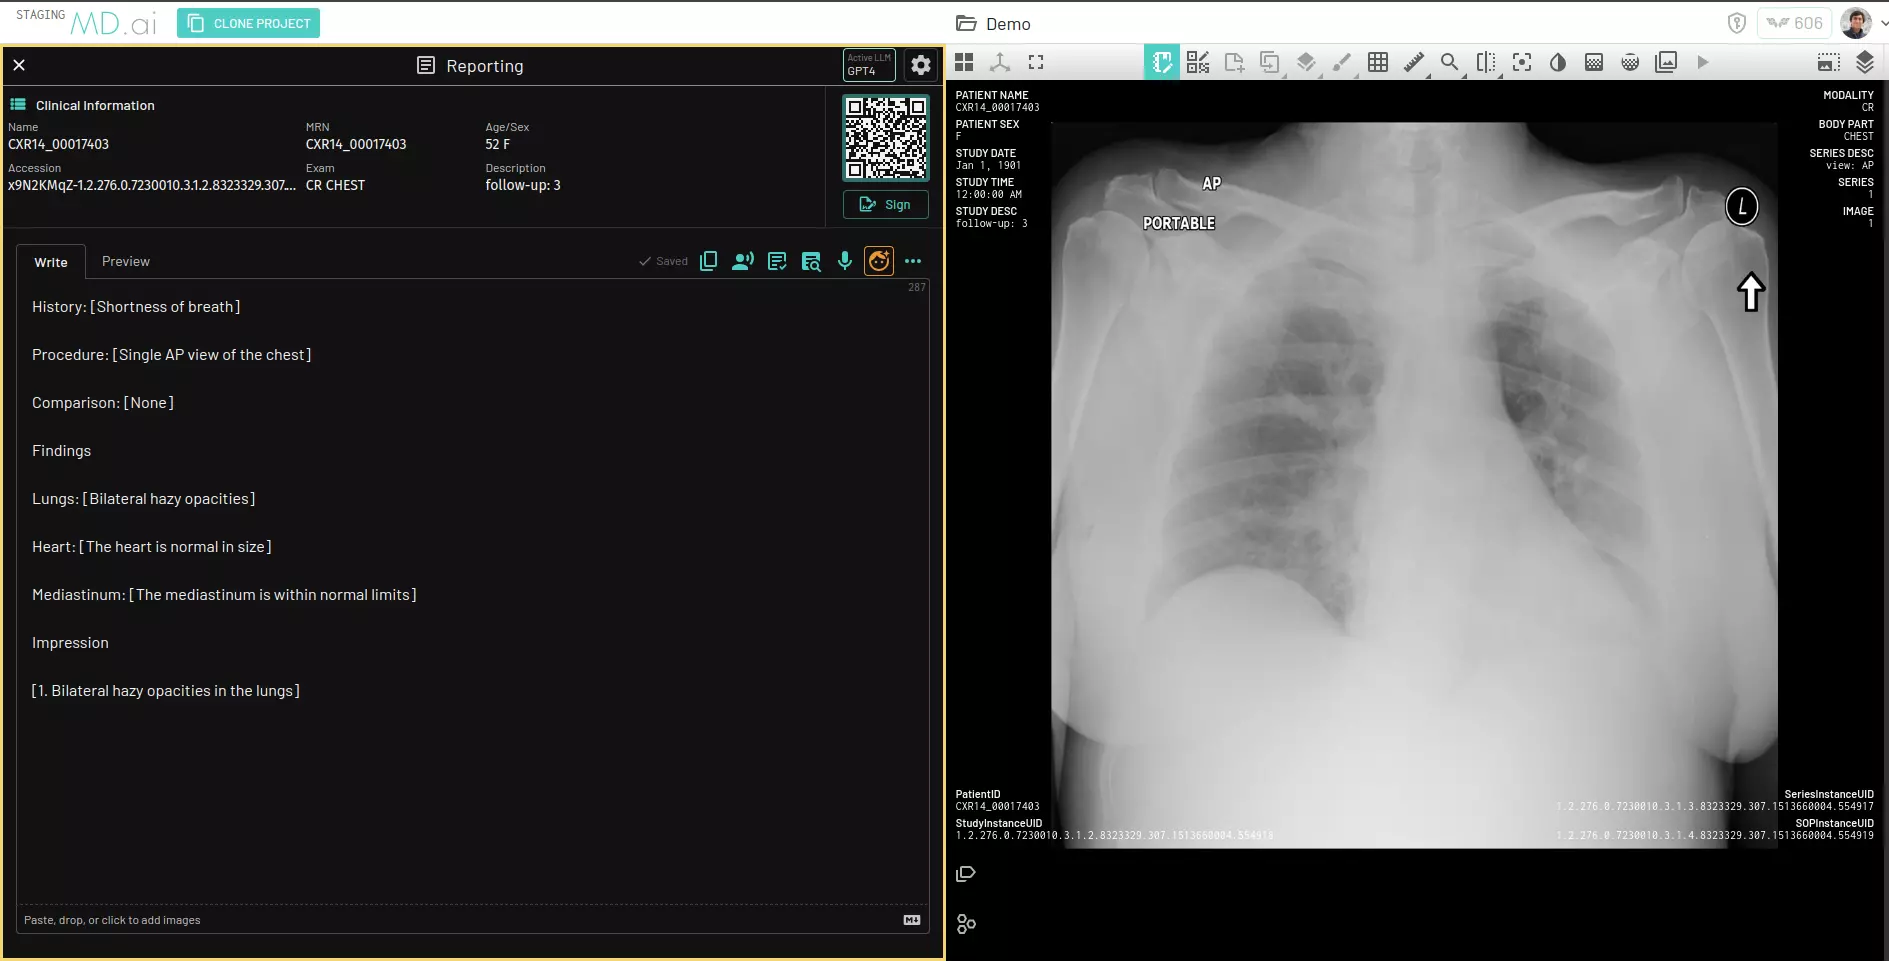

Many of our customers have added a button within their worklists that launches both their image viewer and the MD.ai reporting interface side by side, streamlining the workflow and improving user efficiency.

Here is an example of the reporting system integrated within MD.ai's DICOM viewer and annotation platform as an iframe:

MD.ai Reporting integrated within MD.ai's DICOM viewer